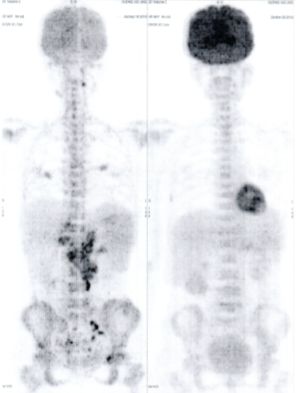

Below are some of the cases, from more than 80 cases we have treated so far with good results. When reading the PET/CT scans, the picture on the left is before treatment, and the picture on the right is after treatment. The intensity of black represents the activity of the cancer, but some black areas are not cancer: brain, heart, radioactive urine in bladder. For the heart, the intensity of black depends on the number of hours of fasting: if more than 10 hours, the heart is not even black, but if fasting is less than 6 hours, it is very black. The intensity of black in the brain can be variable in different scans depending on the brain activity at the time of the scan. The intensity of black in the radioactive urine can also be variable due to the hydration of patients and the time of injection of diuretic.

CASE NO: 3 (PROSTATE CANCER)

A middle-aged man with castration resistant prostate cancer, having failed all currently available cancer treatment, was very weak, and getting worse every day. The PET/CT scan showed he had massive bone metastases. After a few treatment, all the bone metastases went into remission. About 6 months later, he is still in remission.

CASE NO: 4 (PROSTATE CANCER)

A middle-aged man with castration resistant prostate cancer and massive bone metastases, failed all currently available cancer treatment, including with the new and expensive drug XTANDI. After a few treatment, most of the bone metastases went into remission, and the remaining ones are less active. Treatment will continue. Cases no: 3 and 4 show that terminal prostate cancer today can be cured with our new cancer treatment.